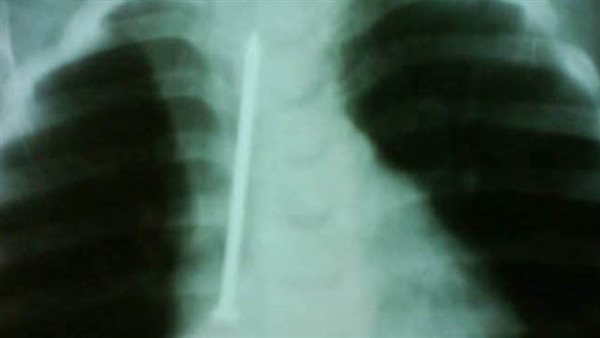

نجح فريق طبي بمستشفى الأطفال التخصصي ببنها، بمحافظة القليوبية، في إنقاذ حياة طفلة ابتلعت مسمارًا بالخطأ، واستقر بالقفص الصدري، حيث أجرى فريق جراحة الأطفال بالمستشفى جراحة عاجلة لطفلة تبلغ من العمر عامًا ونصف ابتلعت مسمارًا معدنيًا بطول 6 سنتيمترات دون أن تظهر عليها أي أعراض أو مضاعفات خطيرة.

وأضاف قائلًا: "كانت الطفلة في حالة طبيعية تمامًا، تتنفس بشكل جيد ولا تعاني من أي صعوبة في البلع، لكن أمام إصرار الأم على أنها بحثت جيدًا في المنزل، قررت إجراء أشعة على صدر الطفلة، لتظهر المفاجأة الصادمة مسمار طويل يمتد بطول القفص الصدري تقريبًا".